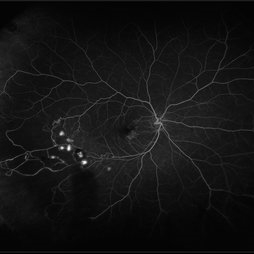

Sickle cell retinopathy (Proliferative) (2 files)

Sickle cell retinopathy (Proliferative) (2 files)

Proliferative sickle retinopathy (1 file)

Proliferative sickle retinopathy (1 file)

Proliferative Sickle Cell Retinopathy (Stage3) (10 files)

Proliferative Sickle Cell Retinopathy (Stage3) (10 files)

Sickle Cell Retinopathy (11 files)

Sickle Cell Retinopathy (11 files)

Sickle Cell Retinopathy SC (6 files)

Sickle Cell Retinopathy SC (6 files)

Sickle Cell (1 file)